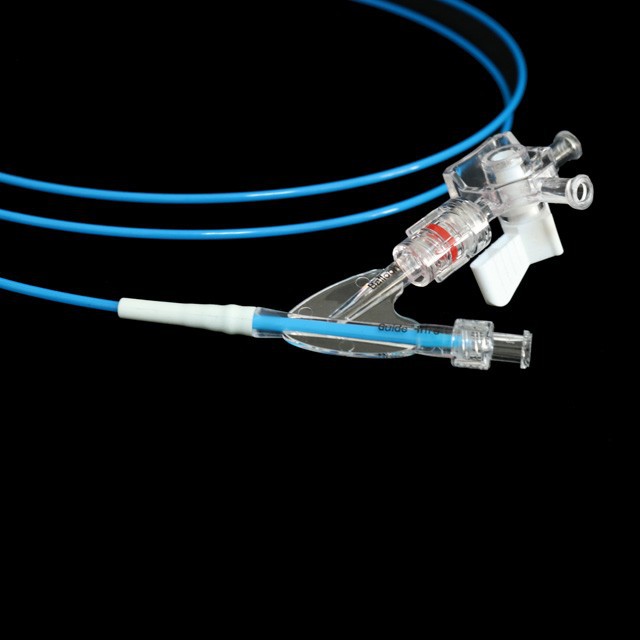

● Elastic yakapfava tip dhizaini, iyo inogona kupinda mukati medu pachinzvimbo chakanangana nechinzvimbo chisina kukuvara {}

● Kukurumidza kudhirowa dhizaini kunobatsira kuderedza kuvhiyiwa nguva .

● Shandisa zvinhu kunze kwenyika zvine simba rekumanikidza kudzvinyirira uye yakachengeteka dhalation .

● Sangano rekugadzira mushure mekutya-mapapiro-mapapiro emapapiro kunopa kukurudzira kwakanakisa uye kuchinjika kudzoka kubva pakushanda chiteshi {{1}

● Kugadzira kurongeka kwehubhu kunoita kuti zvive zvatakapfidza uye nezvakanaka zvakanaka, zvinokatyamadza kupokana nekukasira uye kupfuudza nyore nyore .

● Iyo adigaque mamaki pamigumo miviri yeballoon inogona kupa chaiyo chinzvimbo pasi pe x-ray .

● Pre-input 0 . 035 "kutungamira waya neye nyoro nyoro uye mucherechedzo, iri nyore kufungidzira urefu hwemukati wemukati waya.